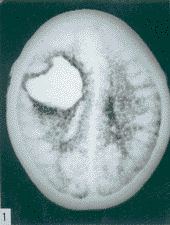

1.確定有無蛛網膜下腔出血。出血急性期,CT確診SAH陽性串極高,安全迅速可靠。出血一周后,CT叮不易診

顱內動脈瘤2.因顱內動脈瘤多位於顱底部WiLLis動脈環,直徑小於1.0C的動脈瘤,CT不易查出。直徑大於1.0cm,注射對比劑後,CT掃描可檢出。MRI憂於CT,動脈瘤內可見流空。MRA可提示不同部位動脈瘤,常用於顱內動脈瘤篩選。三維CT(3D—CT)從不同角度了解動脈瘤與載瘤動脈的關係,為手術夾閉動脈瘤決策提供更多的資料。